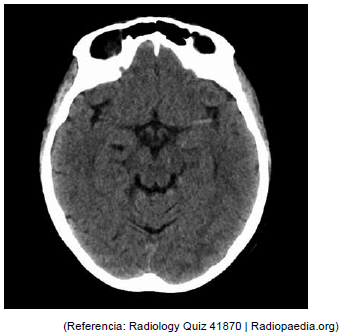

ACO, 70 anos, com antecedente prévio de hipertensão arterial e cardiomiopatia chagásica. Levada por familiares ao pronto-socorro, relatando que ela foi dormir bem por volta de meia noite no dia anterior e hoje, de madrugada, encontraram-na arresponsiva. À admissão hospitalar às 5h30 da manhã, estava hipertensa, com pressão arterial de 181 x 100 mmHg; frequência cardíaca de 68 bpm, saturação em ar ambiente 82%, glicemia capilar de 81mg/dL. Para estabilização hemodinâmica, necessitou prosseguir com intubação orotraqueal, sedoanalgesia e monitorização. Eletrocardiograma em ritmo sinusal. Coletaram-se exames séricos e foi encaminhada ao setor de tomografia. Constatou-se a imagem a seguir. Qual o nome do sinal apresentado nessa tomografia de crânio?